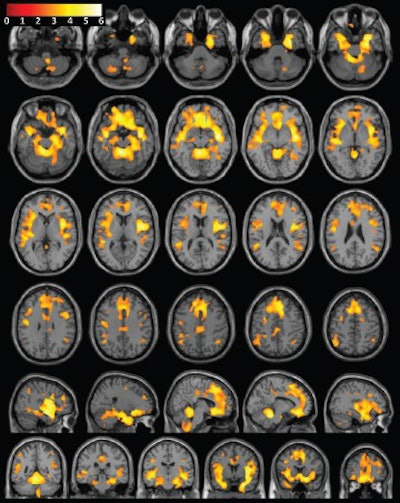

The images showed that women who used stimulant drugs had significantly lower grey-matter volume in the frontal lobe, limbic regions, temporal lobe, and inferior parietal lobule, compared with the healthy female subjects.

Consecutive T1-weighted MRI of the brain with superimposed population-level T-value map shows significantly greater grey-matter volume in female control subjects than in women with substance dependence, after correction for age, brain size, and years of education. Image courtesy of Radiology.The researchers also looked at how these brain volume differences correlated with behavior. In the women who used stimulant drugs, lower gray-matter volumes were linked with greater impulsivity and also more severe drug use.